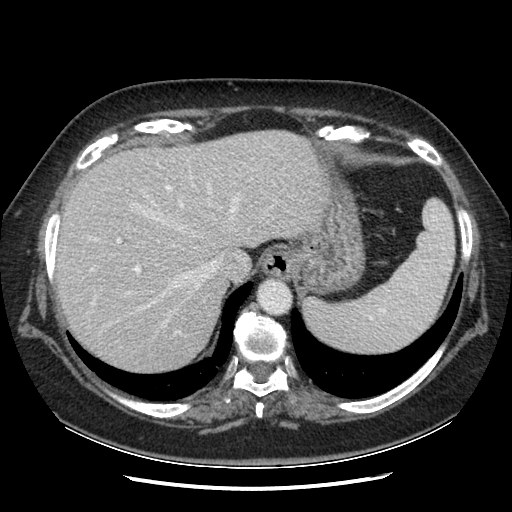

Original VENOUS CT scan

Full window (WL 1023.5, WW 4095 β†’ Low βˆ’1024, High +3071)

Lung window (WL -600, WW 1500 β†’ Low βˆ’1350, High +150)

Mediastinum window (WL 40, WW 400 β†’ Low βˆ’160, High +240)